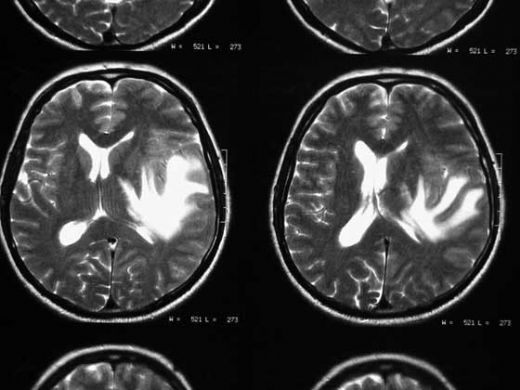

Beyin Metastazının Tanı Yöntemleri Beyin metastazının tanısı, çeşitli yöntemlerle konulabilir. Bu yöntemler arasında:

Kafa içi basıncın artması, baş ağrıları, nörolojik belirtiler (görme bozuklukları, denge kaybı gibi) beyin metastazı olan hastalarda sıkça görülen belirtilerdir. Bu belirtilerin varlığı, genellikle hastaların tanı sürecini hızlandırır, ancak tanı koymak bazen zorlayıcı olabilir. Görüntüleme yöntemleri (MR, BT) bu süreçte kritik rol oynar.